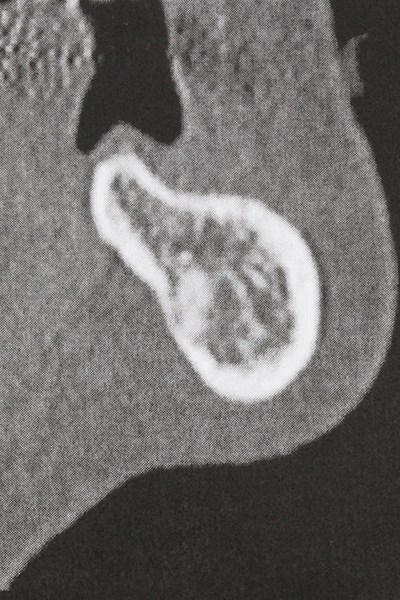

Abb. 17a: CT-Aufnahme eines wachstumsprogredienten Osteoms in unmittelbarer ...

Abb. 17b: Lagebeziehung zum Alveolarkanal mit Nervirritation (laterale und koronare Ansicht).